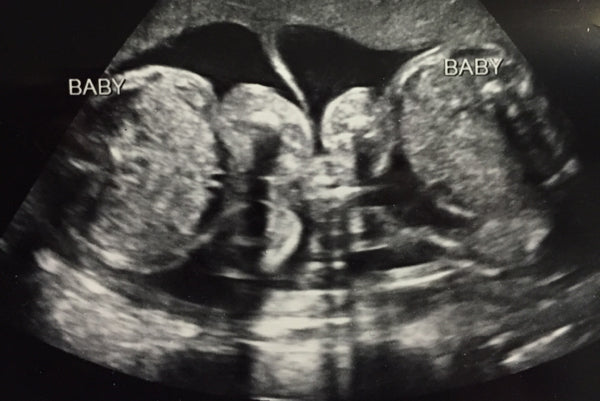

When the doctor first showed me the ultrasound, it was very clear the babies were in separate sacs, and looked like they would both form their own placentas. As far as I knew, this meant they would be fraternal. I turned to my doctor and said, "so they are fraternal twins then?" Her response, "you actually won't know for a while." WHAT? HOW?! There is a chance they could be identical!?! Do you know how awesome that would be?! YAY! All thoughts had by me within seconds of this new observation. So what did I do immediately when I got home? I researched all the different types of ways that my babies may possibly end up identical, duh. Did you know that there are something like 7 types of twins? Conjoined and mirror-image twins make it on that list. So, instead of making you do all the work, I'll at least sum up the difference between fraternal and identical twins, and how you know.Fraternal Twins: